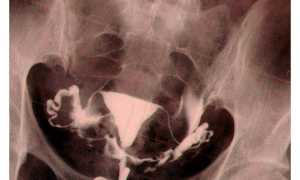

- УЗИ. Это самый популярный и достоверный способ определения пола вашего будущего крохи. Он безопасен для плода, но достоверный результат может быть получен только по истечении 23 недель беременности. На более ранних сроках существует погрешность (15-18 недель), а до этого времени способ и вовсе не информативен.

- Биопсия хориона. Таким способом половая принадлежность малыша может быть определена уже по истечении 1,5 месяцев беременности. Процедура представляет собой намеренное извлечение нескольких плацентарных клеток специальной иглой, вводимой в матку. Результат при этом стопроцентный.

Важно! Биопсия хориона проводится исключительно по специфическим медицинским показаниям! Такой метод может спровоцировать проблемы с развитием плода и рождением. Поэтому категорически не рекомендуется проводить ее только с единственной целью – узнать пол ребенка.

- Анализ ДНК. Этот метод способен определить пол ребенка начиная с 5 недели беременности, а к 8 неделе его результаты достоверны практически на 100%. Для этого беременной женщине необходимо сдать кровь. В лаборатории ее исследуют на наличие Y хромосомы. Если она есть, то будущим родителям необходимо готовиться к тому, что у них родится сын. Если эта хромосома в крови не обнаружена – будет дочь.